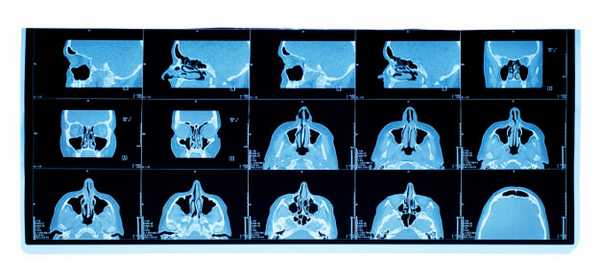

КТ носа позволяет оценить носовую кость и хрящи в трех проекциях - коронарной, аксиальной и сагиттальной. Врач можно выполнить трехмерную реконструкцию костей лицевого скелета для того, чтобы понять, если у больного переломы, травмы, врожденные аномалии носовой перегородки, костные наросты и деформации. Основным показанием для применения данного вида томографии будут любые костные повреждения носа.

Компьютерная томограмма пазух носа

Компьютерная томография пазух носа позволяет изучить послойное строение этого участка черепа. Рентгеновские лучи, пропущенные через полые структуры, обрабатываются с помощью компьютерного обеспечения, после чего создается их трехмерная модель.

Теперь можно перейти к рассмотрению основного вопроса. Итак, снимки разных срезов пазух носа, сделанные под разными углами, дают возможность диагносту изучить исследуемый объект в разных плоскостях. На трехмерном изображении можно четко рассмотреть контуры всех составных частей пазух, а также их плотность, структуру, степень минерализации и объем.